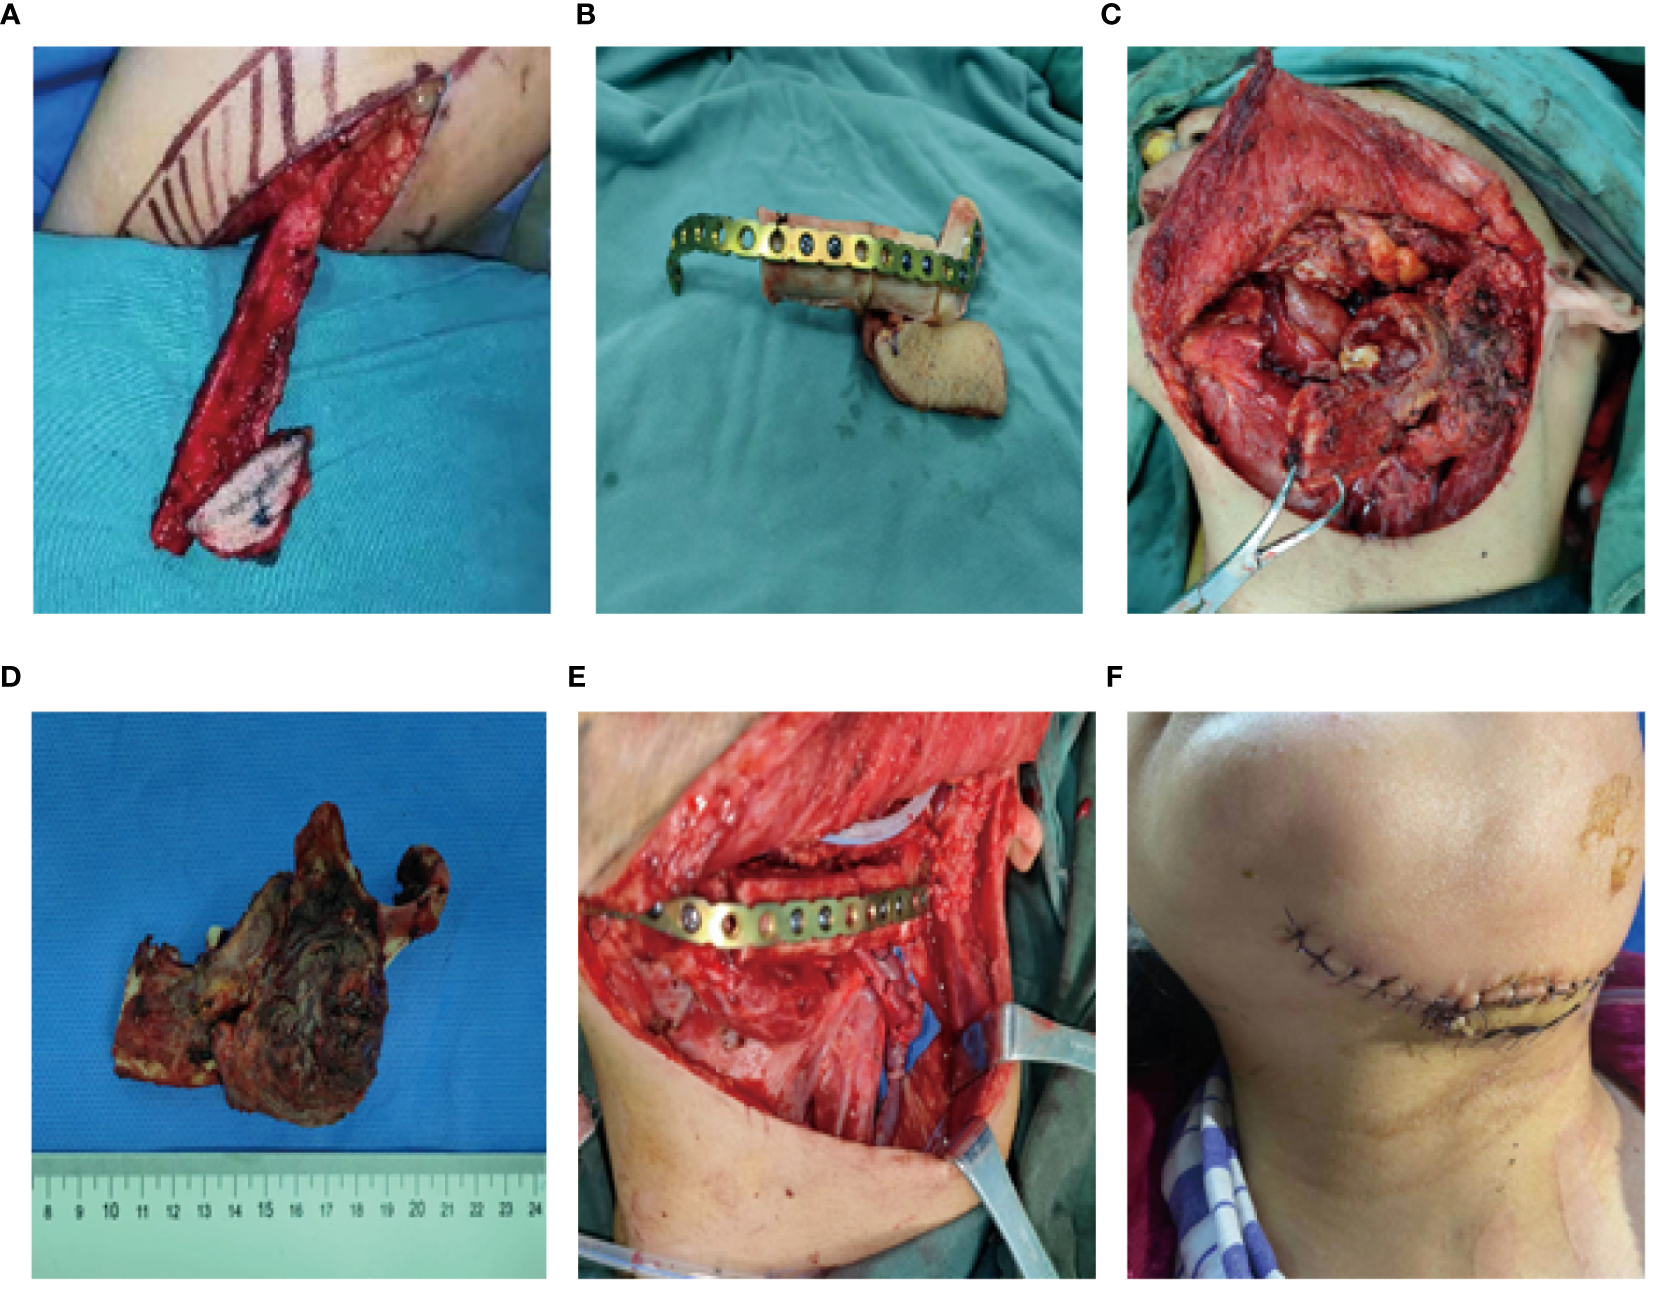

A 56-year-old female underwent surgery for ameloblastoma in the left mandible 2 years previously. Specialist examination revealed that the patient had swelling on the left face and neoplasm in the area surrounding the left mandibular angle and ramus, approximately 5.0 × 4.0 cm measuring in size. The patient also had a mild limitation in mouth opening, and 36, 37, and 38 were not detected in the oral cavity. According to the patient’s previous medical records and consultation report from the pathology department of our hospital, the pathological diagnosis of the patient was confirmed as ameloblastoma (Figure 1). The patient was diagnosed with ameloblastoma upon admission and scheduled to undergo partial mandibular resection and fibular osteocutaneous flap repair. She underwent CTA examination of the maxillofacial and the left calf prior to surgery. The obtained CTA data were imported into a software workstation for 3D reconstruction and subsequently downloaded onto a holographic display (Figures 2, 3). During the operation, the left calf was automatically positioned according to the holographic display, and the perforator vessels were dissected in real-time (Figure 4). Fibular osteocutaneous flaps were prepared to repair the mandible, and direct sutures were placed at the donor site (Figures 5, 6). After the operation, the flap fully survived, and during the 6-month follow-up, the patient expressed satisfaction with the reconstructive outcome.

Figure 4

Intraoperative schematic diagram of mixed reality technology.

Figure 5

Repair and reconstruction of peroneal musculocutaneous flap. (A–E) Intraoperative reconstruction with fibula musculocutaneous flap; (F) Reconstruction outcome after the surgery.